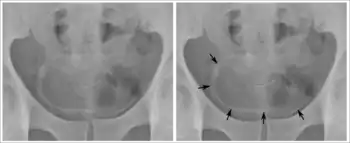

_histopathology.JPG.webp)

Identification of eggs in stools

Diagnosis of infection is confirmed by the identification of eggs in stools. Eggs of S. mansoni are about 140 by 60 µm in size and have a lateral spine. The diagnosis is improved through the use of the Kato technique, a semiquantitative stool examination technique. Other methods that can be used are enzyme-linked immunosorbent assay, circumoval precipitation test, and alkaline phosphatase immunoassay.[34]

Microscopic identification of eggs in stool or urine is the most practical method for diagnosis. Stool examination should be performed when infection with S. mansoni or S. japonicum is suspected, and urine examination should be performed if S. haematobium is suspected. Eggs can be present in the stool in infections with all Schistosoma species. The examination can be performed on a simple smear (1 to 2 mg of fecal material). Because eggs may be passed intermittently or in small numbers, their detection is enhanced by repeated examinations or concentration procedures, or both. In addition, for field surveys and investigational purposes, the egg output can be quantified by using the Kato-Katz technique (20 to 50 mg of fecal material) or the Ritchie technique. Eggs can be found in the urine in infections with S. haematobium (recommended time for collection: between noon and 3 PM) and with S. japonicum. Quantification is possible by using filtration through a nucleopore filter membrane of a standard volume of urine followed by egg counts on the membrane. Tissue biopsy (rectal biopsy for all species and biopsy of the bladder for S. haematobium) may demonstrate eggs when stool or urine examinations are negative.[35]